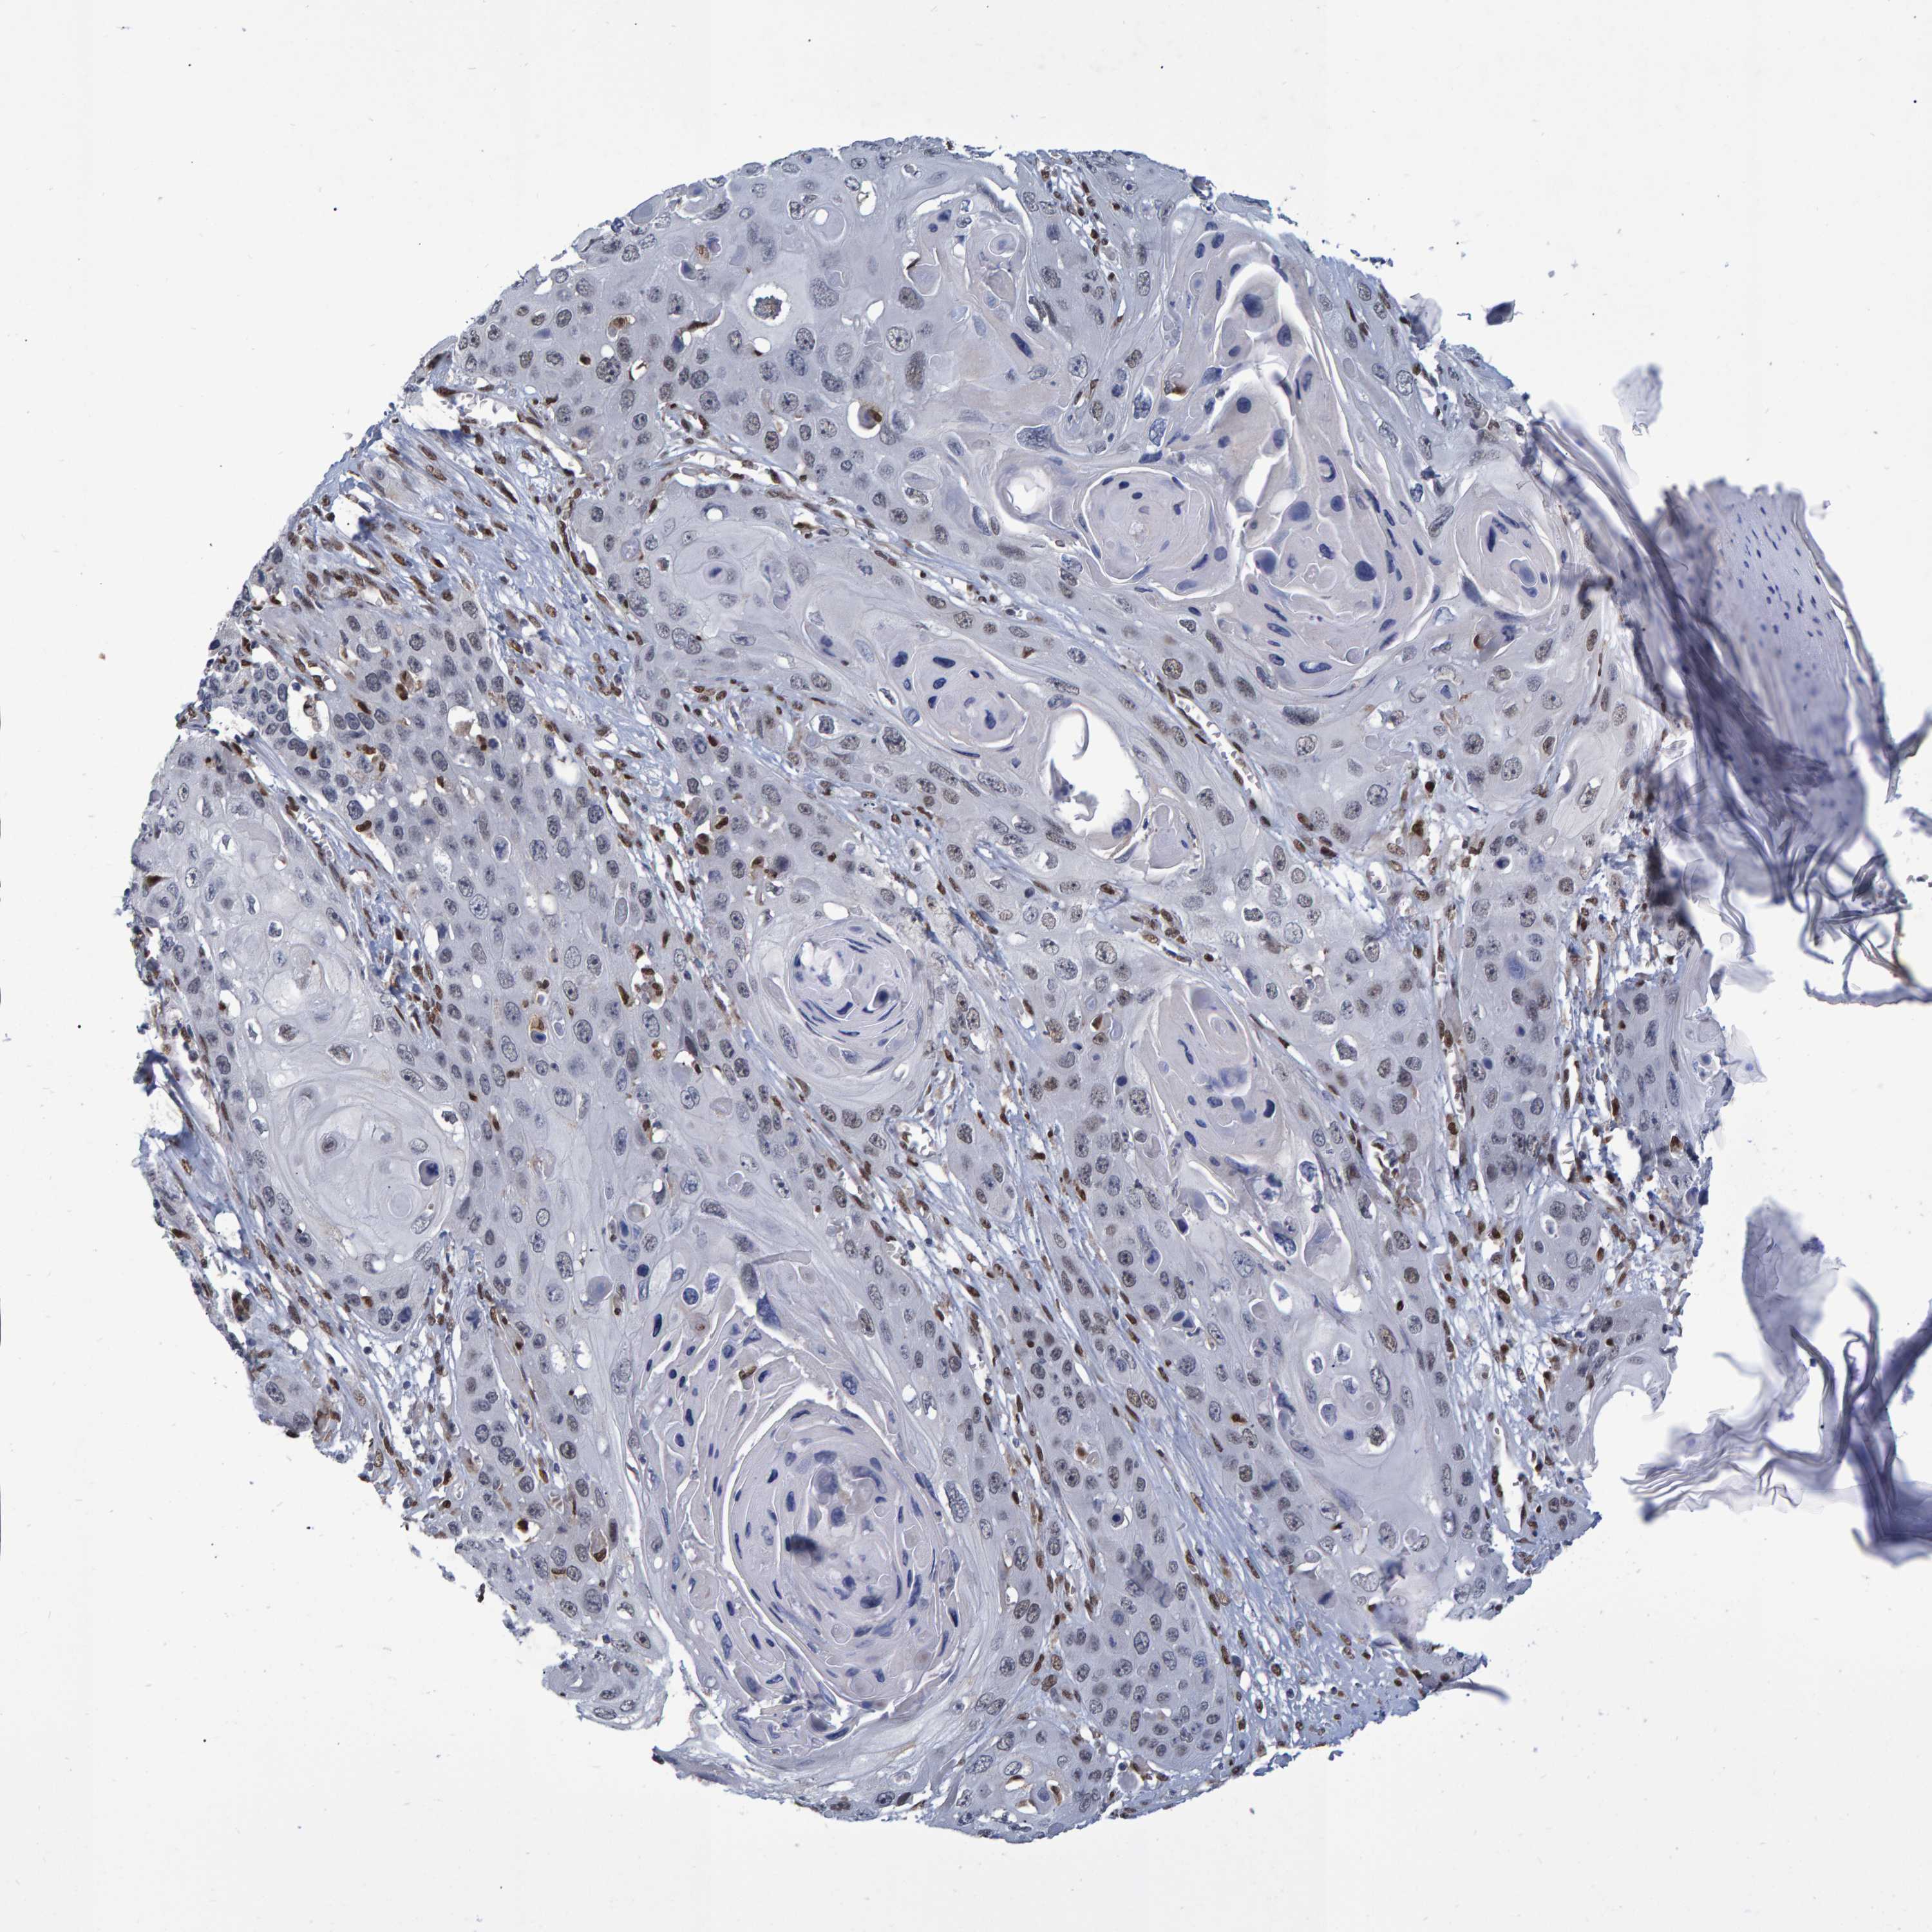

SKIN CANCER - Protein expressioni

A mouse-over function shows sample information and annotation data. Click on an image to view it in a full screen mode. Samples can be filtered based on level of antibody staining by selecting one or several of the following categories: high, medium, low and not detected. The assay and annotation is described here.

Each image is clickable and will lead to virtual microscopy that enables deeper exploration of all samples and also displays staining intensity scores, fraction scores and subcellular localization as well as patient and tissue information for each sample.

Antibody HPA019123

Antibody CAB022602

Staining

High

Medium

Low

Not detected

Intensity

Strong

Moderate

Weak

Negative

Quantity

>75%

75%-25%

<25%

None

Location

Nuclear

Cytoplasmic/membranous

Cytoplasmic/membranous,nuclear

Squamous cell carcinoma in situ, NOS

Squamous cell carcinoma, NOS

Squamous cell carcinoma, metastatic, NOS

Basal cell carcinoma